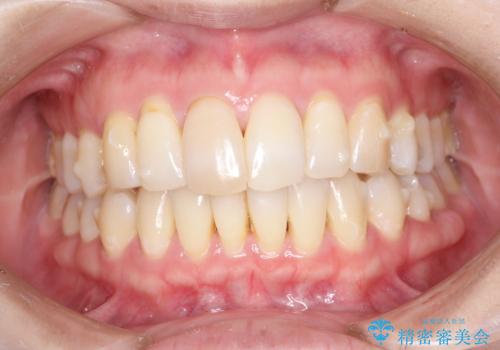

再矯正をインビザラインで目立たず手軽に

- 以前矯正をしていたが、わずかに後戻りをしてしまったのを主訴に来院されました。

装置はなるべくつけたくないとのことで、インビザラインにて治療することとなりました。

以前ワイヤー矯正をされていた方は、装置をつけての再矯正を希望されない方もいます。

その場合にインビザラインをお勧めさせていただいております。

後戻りがわずかな場合は、期間も短くて済む場合があります。